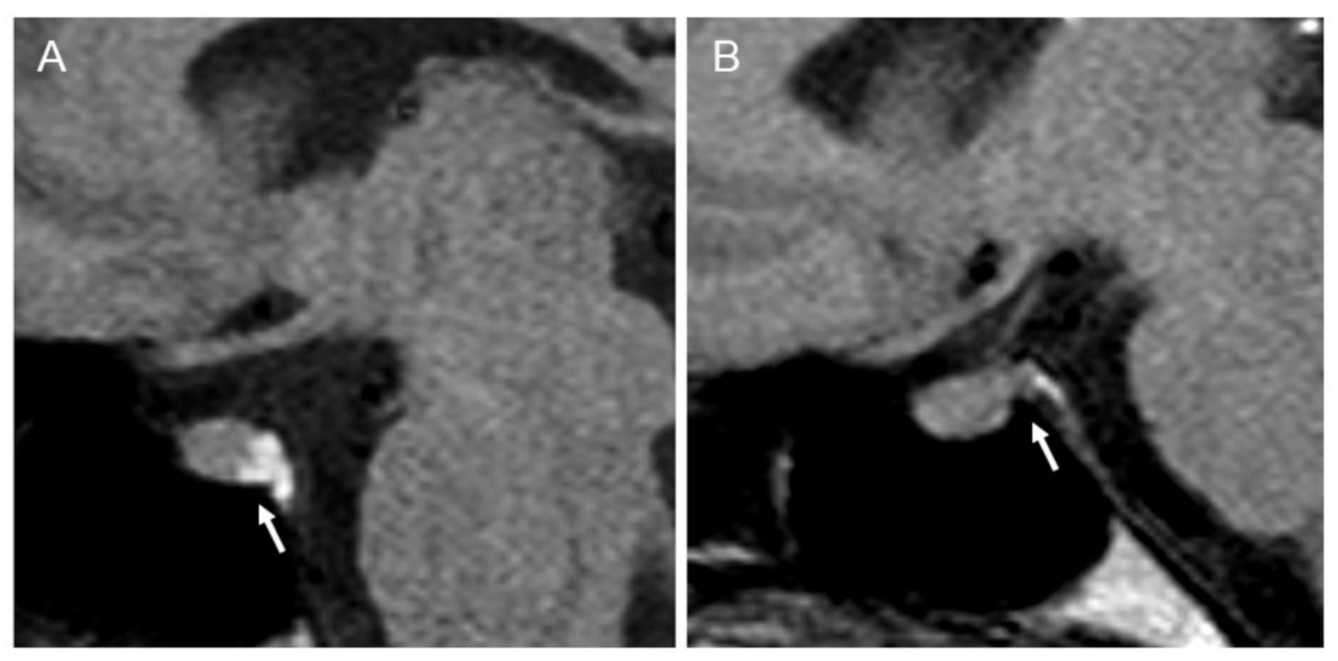

2.1. Clinical and Radiological Assessments

3.1. Clinical and Radiological Assessments